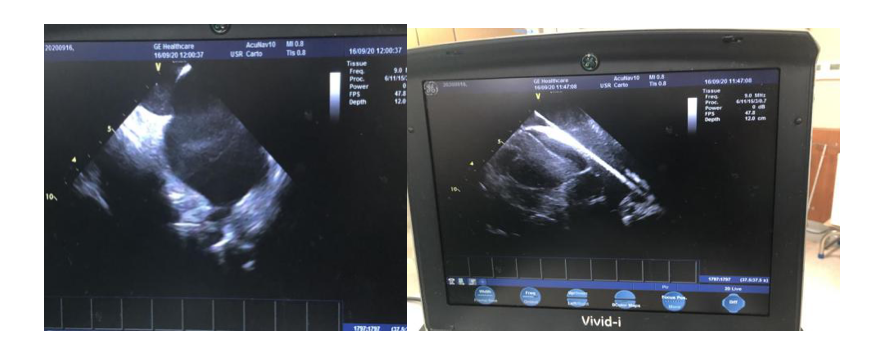

心内超声下直视房间隔穿刺